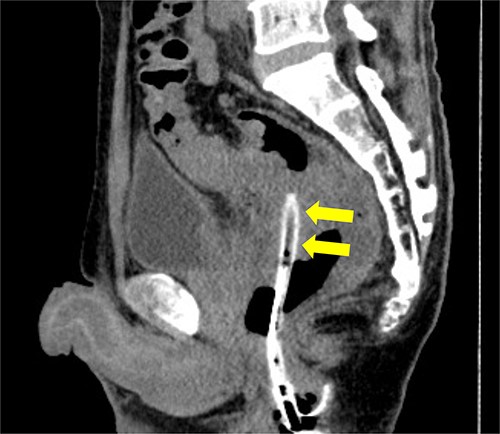

Subsequently, we performed transrectal drainage of the abscess in the lithotomy position without endoscopy. After the incision of the excluded rectal mucosa at 7 cm from the anal verge by the electric scalpel and penetration of the abscess wall by the Kelly clamp, a massive purulent discharge was observed. Next, a transanal rectal drainage tube (MIT drain®, effective length 12 cm; Create Medic Co., Ltd, Yokohama, Japan) was inserted into the abscess cavity without the use of a guide wire, and saline irrigation was performed. After transrectal drainage, the patient’s pain and inflammatory laboratory findings improved rapidly. Pelvic CT showed shrinkage of the cavity 3 days after the drainage (Fig. 3). Bacterial culture test and cytology of the drainage contents revealed negative growth and no malignancy, respectively. The biopsy results showed moderately differentiated tubular adenocarcinoma. The inserted tube was removed on the seventh day after the drainage, and the patient was discharged on the eighth day. In the outpatient department, total colonoscopy revealed that the exclusion from outside the rectal wall on the anal side of the tumor diminished, and the incised mucosa healed as a scar. Ink sticks were marked near the scar on behalf of the combined resection of the tumor. Pelvic CT revealed that the pelvic abscess had disappeared 1 month after drainage (Fig. 4).

Pelvic CT performed 3 days after drainage in the sagittal section. Abscess cavity remarkably shrunk (arrowheads).